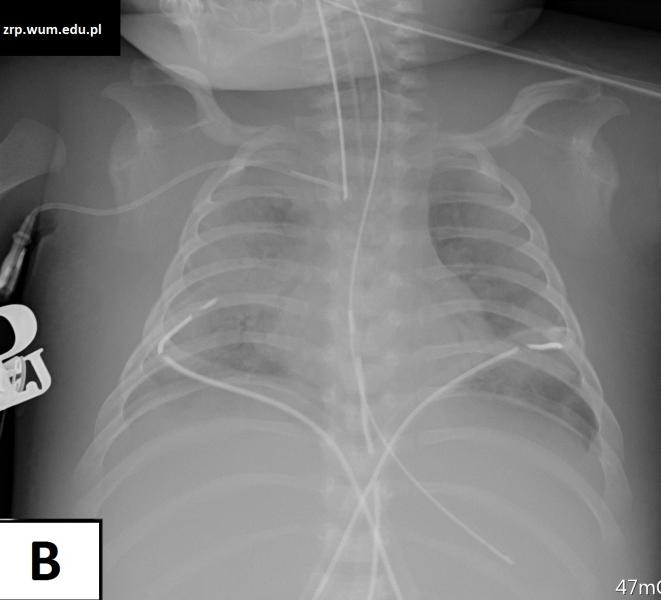

Przypadek 46: Dziewczynka w 1. m-cu życia po operacji kardiochirurgicznej (Tetralogia Fallota), ze znacznym pogorszeniem stanu klinicznego w ciągu kilku godzin.

Rozpoznanie: Wykonano zdjęcia RTG klatki piersiowej w odstępie kilku godzin (wyjściowe - A, i kontrolne - B) - w badaniu kontrolnym znaczne pogorszenie powietrzności płuc - masywne zagęszczenia miąższowe -obraz przemawia za obrzękiem płuc.

Pytanie: Jak różnicuje się obrzęk płuc i zapalenie płuc? Nazwij dreny, cewniki, sondy widoczne na zdjęciach.